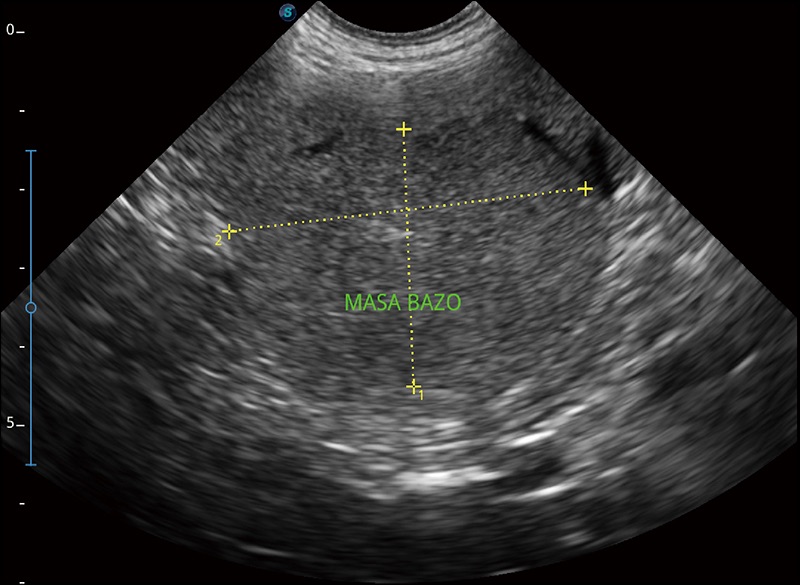

扩展成像

支持线阵和凸阵探头,一键操作即可获得更宽的图像视野

实时宽景成像

可实时观察感兴趣区域和病变位置